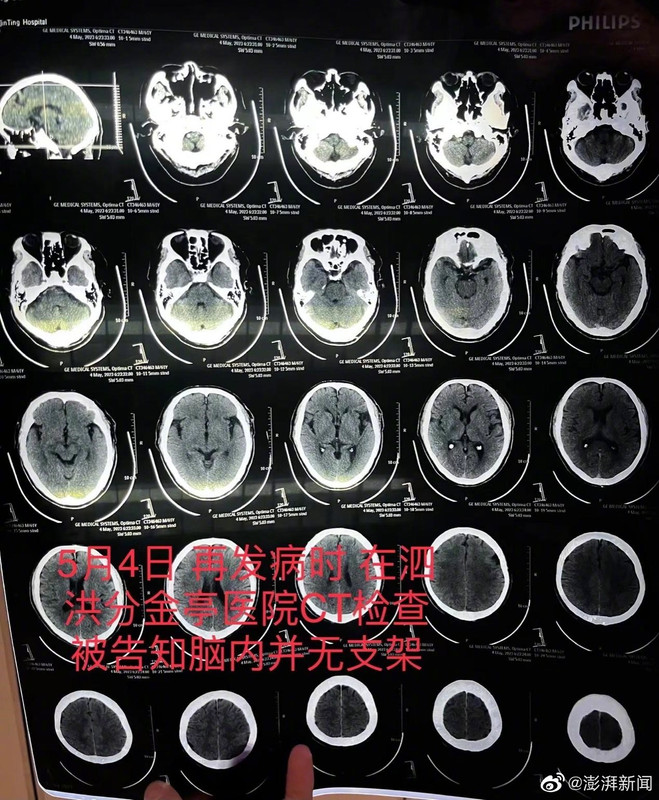

#老人突发脑梗发现医生隐瞒未植入支架#【宿迁一患者因脑梗去世,医生承认此前未成功植入脑血管支架并隐瞒】#医生隐瞒未植入支架称觉得下不了台#因父亲突发严重脑梗症状送医抢救,朱先生才发现,不久前医生称成功植入父亲颅内血管的高价进口支架竟然“消失”了。朱先生说,眼看事态败露,涉事的操刀医师方才承认,此前的手术未能成功放置支架。朱先生提供的录音中,涉事医生称,“我做了这么多手术,没做成的时候很少,当时这个支架没放成,我觉得很打脸,感觉有点不好看,下不了台。”

6月7日,朱先生父亲因动脉血栓堵闭致大部分脑干坏死,不幸去世。朱先生表示,他们将就涉事医院和医护人员故意隐瞒支架未能植入事实、伪造病历虚构手术经过、未装支架却收取费用等情况,向当地法院提起民事诉讼,追究医院和医生医疗过失责任。朱先生认为,院方和相关医护人员均应承担相应的行政责任和赔偿责任,构成犯罪的还应承担刑事责任。

图片

【医生称存侥幸心理怕处分】#老人突发脑梗发现医生隐瞒未植入支架#齐某称当时确有侥幸心理,对于未能安装支架却仍收取费用,其表示,“支架没有用,但也浪费掉了。你说不收费,去哪儿出这个东西?那还得让医院贴钱,(我)也怕处分。”收据显示该进口颅内支架47000元。